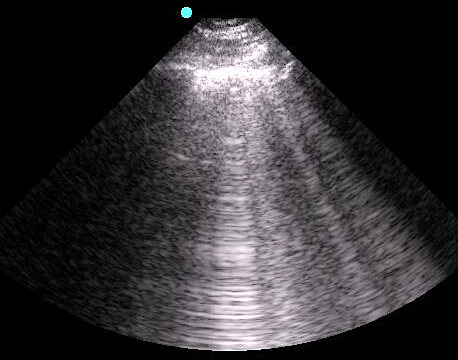

- Figure 4. A-lines

Video 1. A-lines - Occur from the emitted US wave reflecting back and forth between the transducer and the pleural line

- The distance from transducer to pleural line is the same as between the equidistant intervals separating each subsequent A-line.

- The artifacts’ brightness decreases with depth as energy is lost through repeated reflections.